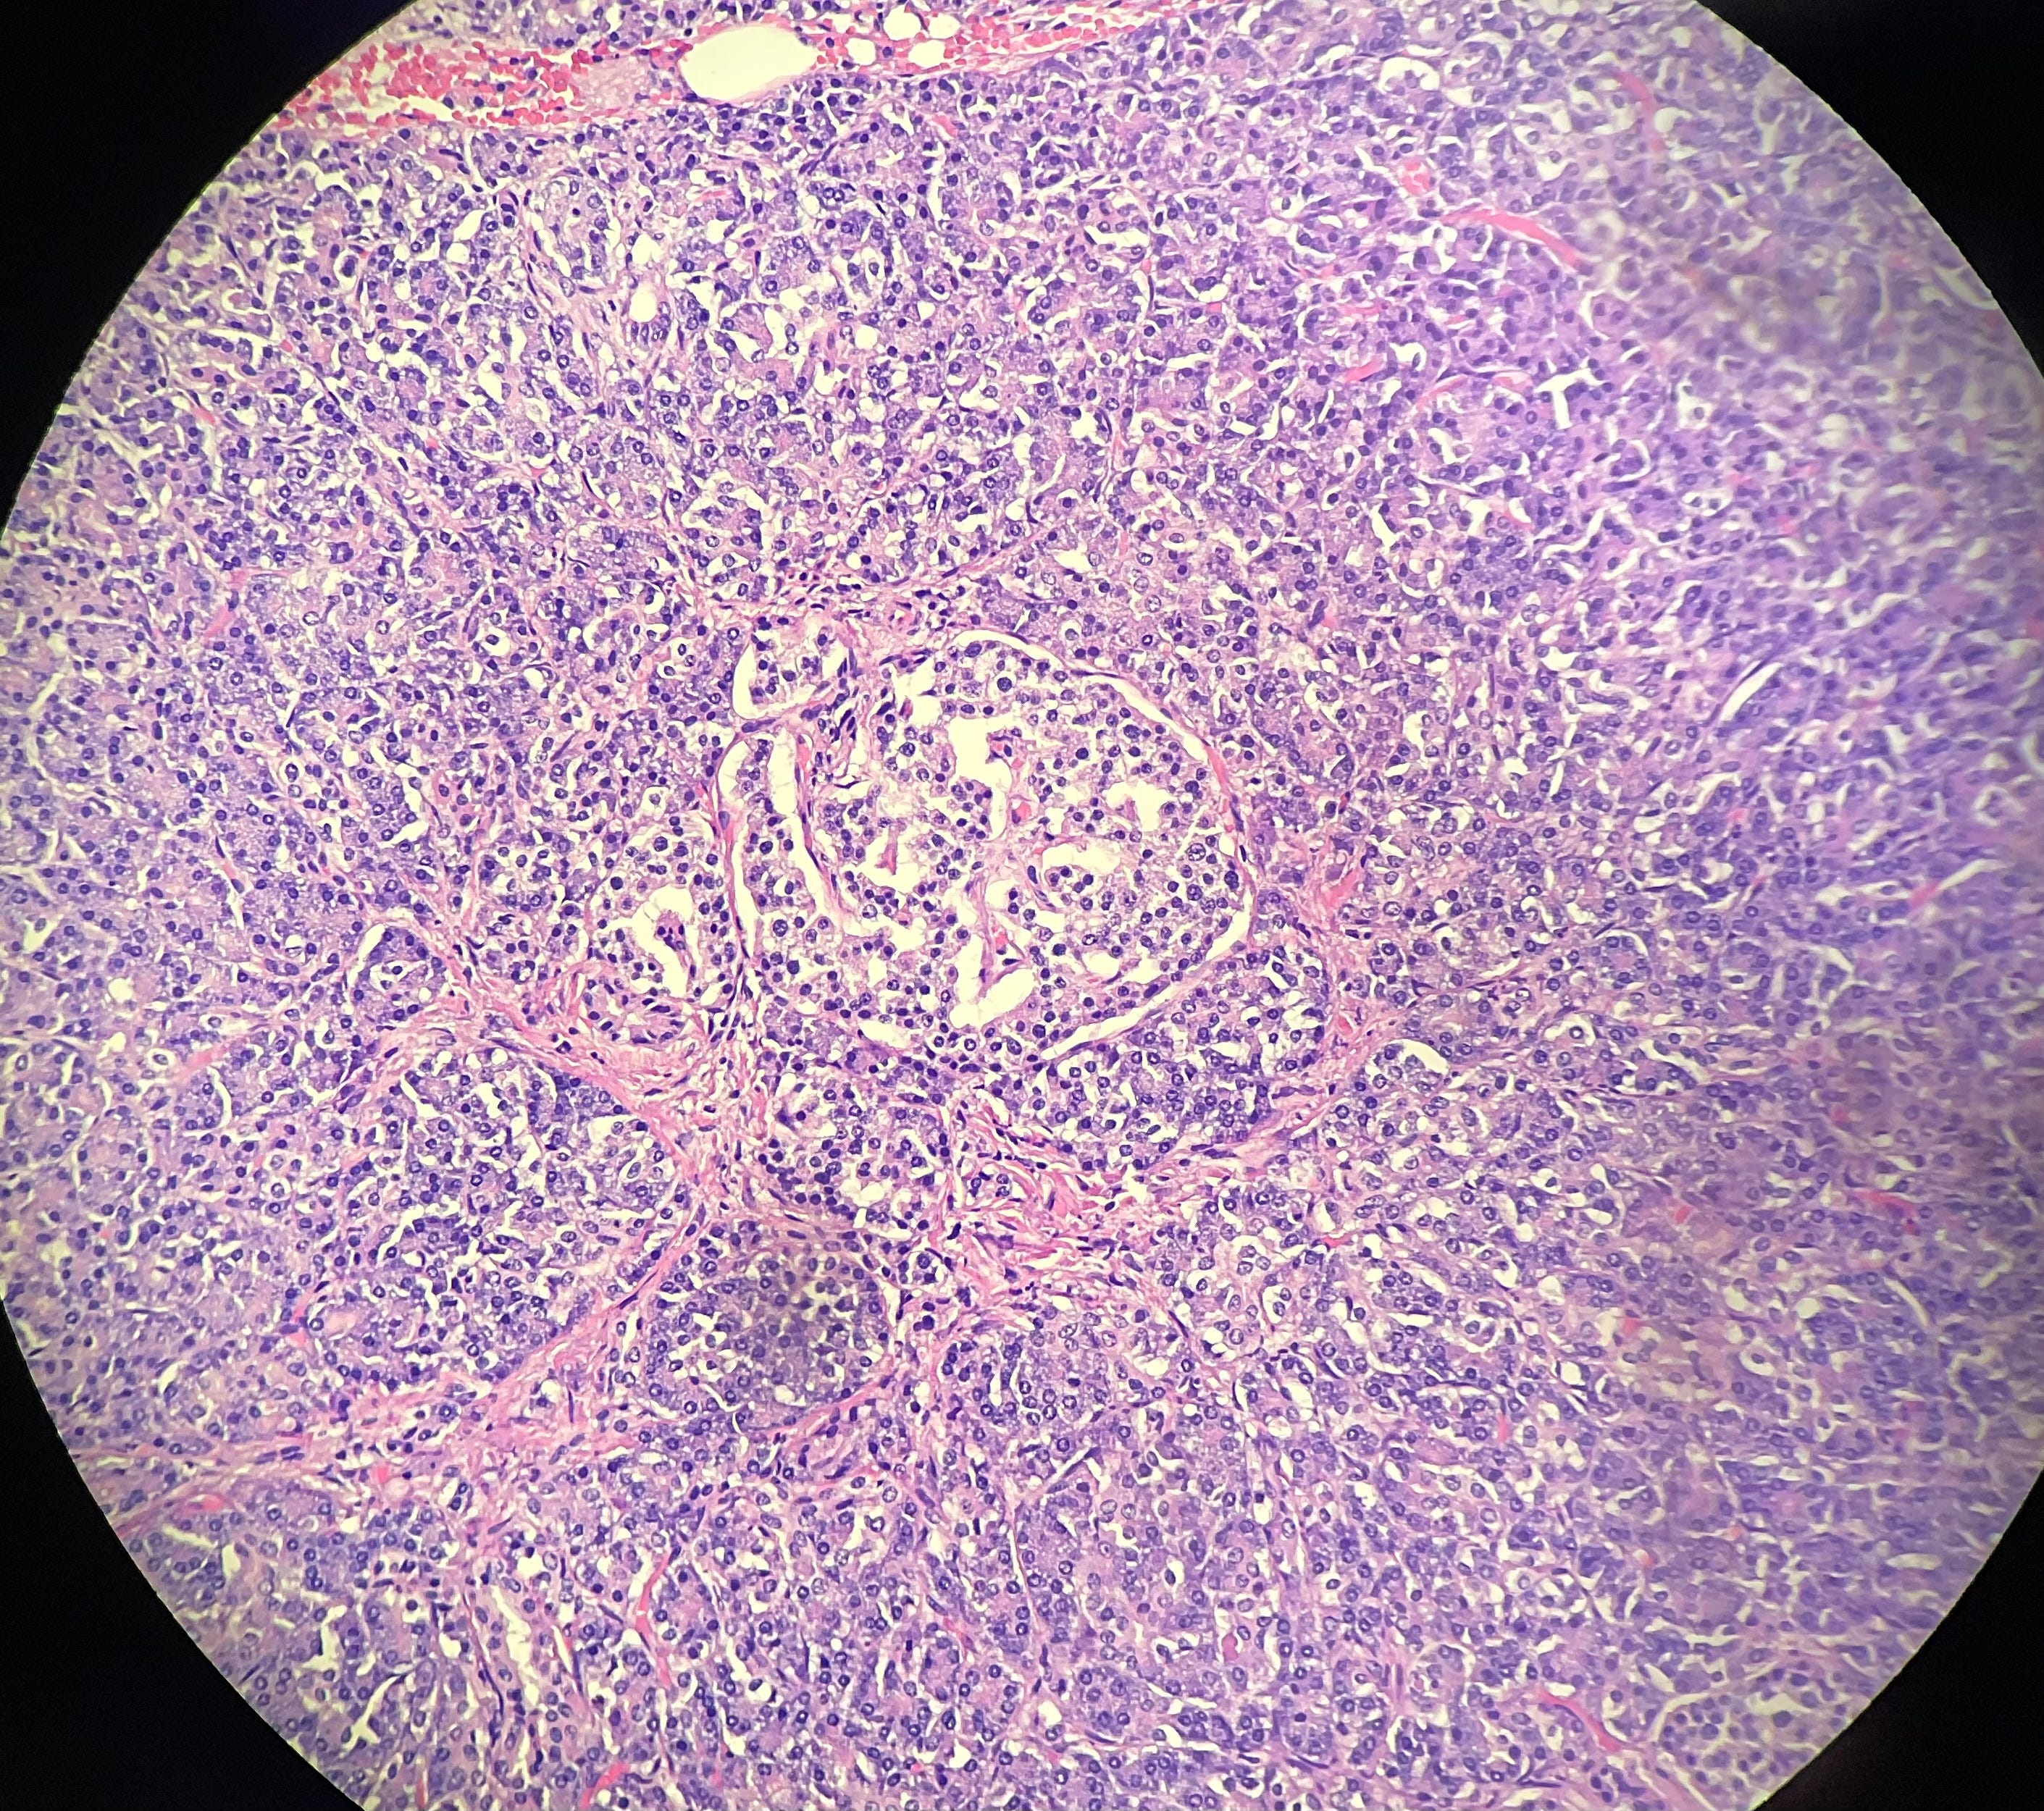

I was working on some microscopic examination slides on Friday and saw a really nice example of pancreatic histology (also known as the microscopic anatomy of the pancreas). Why is this uncommon in the field of forensics? Because when the body dies, the cell walls begin to break down, a process known as autolysis. The problem in particular with the pancreas is that when those cells break down they release the same enzymes used for digestion of the food we eat. In other words, the pancreas digests itself after death and we don’t often get a great view of it. But for whatever reason, this person’s pancreas held up and now I will show you one of my favorite structures in the pancreas. Of course, as you look at this image you’re probably thinking ‘This looks like one of those dot pattern things they make me try to find numbers in at the eye doctor.’ But this is a low power magnification field of the pancreas. Let me help you a little more:

The circled structure is known as an Islet of Langerhans. Dr. Langerhans was a pathologist in the 1800s that named this (and many other things) in particular for microscopic anatomy. Without these structures we could not live; these are endocrine cells that produce the immensely important hormones of insulin, glucagon, and somatostatin. Let’s take a closer look:

I think it’s pretty clear that we are looking at the rounded structure in the middle of the photo that has slightly lighter colored cytoplasm compared with the cells around it. This a singular Islet and you cannot tell by looking at it if this is producing insulin or not. Now, of course while insulin gets the most fanfare with its function of getting glucose into cells for energy, Islets can also be composed of cells that produce glucagon and somatostatin. Glucagon is a hormone that raises blood sugar when levels are getting low or when increased glucose is needed. Somatostatin can inhibit both insulin and glucagon release.